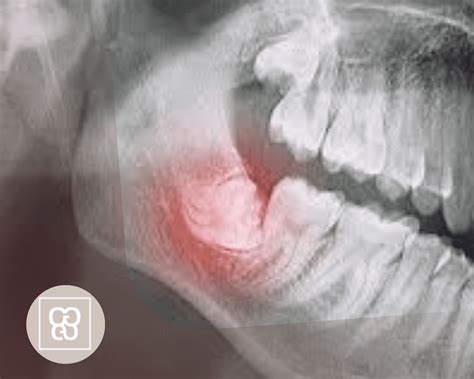

- Malposición: Cuando la muela crece en una posición incorrecta, empujando a otros dientes.

- Infecciones: Cuando la muela retenida causa procesos infecciosos e inflamatorios.

- Extracción con cirugía: Generalmente se realiza si la muela está incluida o presenta complicaciones.